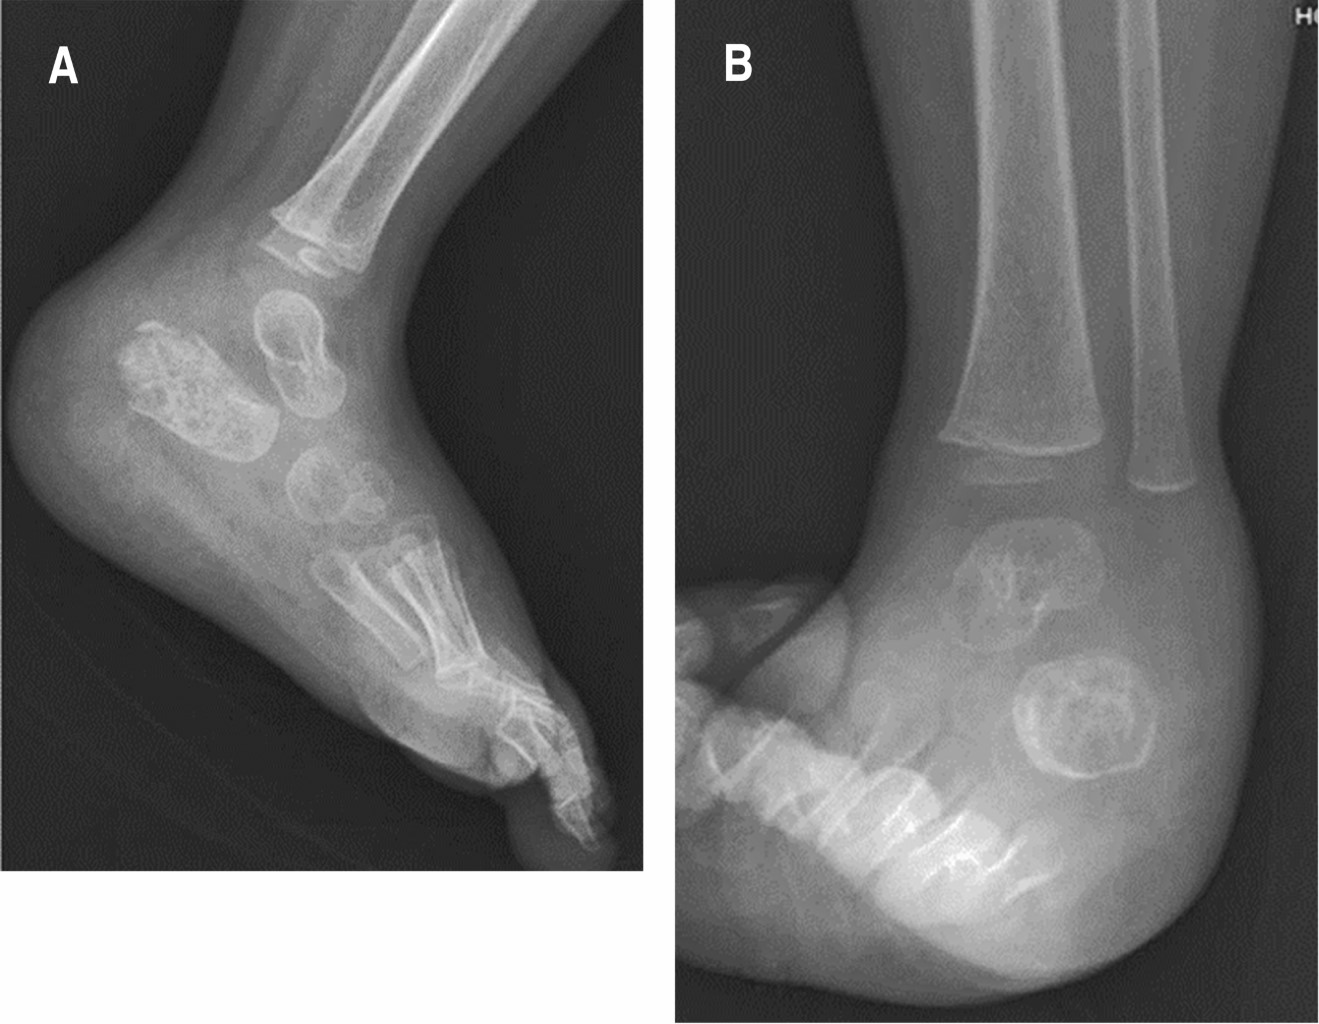

Tres meses posteriores al egreso acude a consulta donde se encuentra herida con adecuado estado de cicatrización, sin presencia de exudado, eritema o dehiscencia de la herida. Acude con un control radiográfico en el cual observamos una proyección tangencial y lateral de calcáneo en donde se aprecia formación de tejido óseo en interior de calcáneo, sin solución de continuidad ósea, congruencia articular conservada (Figura 5).

Dieciocho meses después de su egreso, el paciente acude a valoración por nuestro servicio. Se encuentra en adecuadas condiciones generales, heridas con adecuado estado de cicatrización en proceso de remodelación, se observa además marcha bipodálica, plantígrada, independiente, sin presencia de claudicación, sin presencia de síntomas sistémicos. En radiografía dorsoplantar y lateral de pie se observa formación de tejido óseo en calcáneo sin datos sugestivos de osteomielitis (Figura 6).